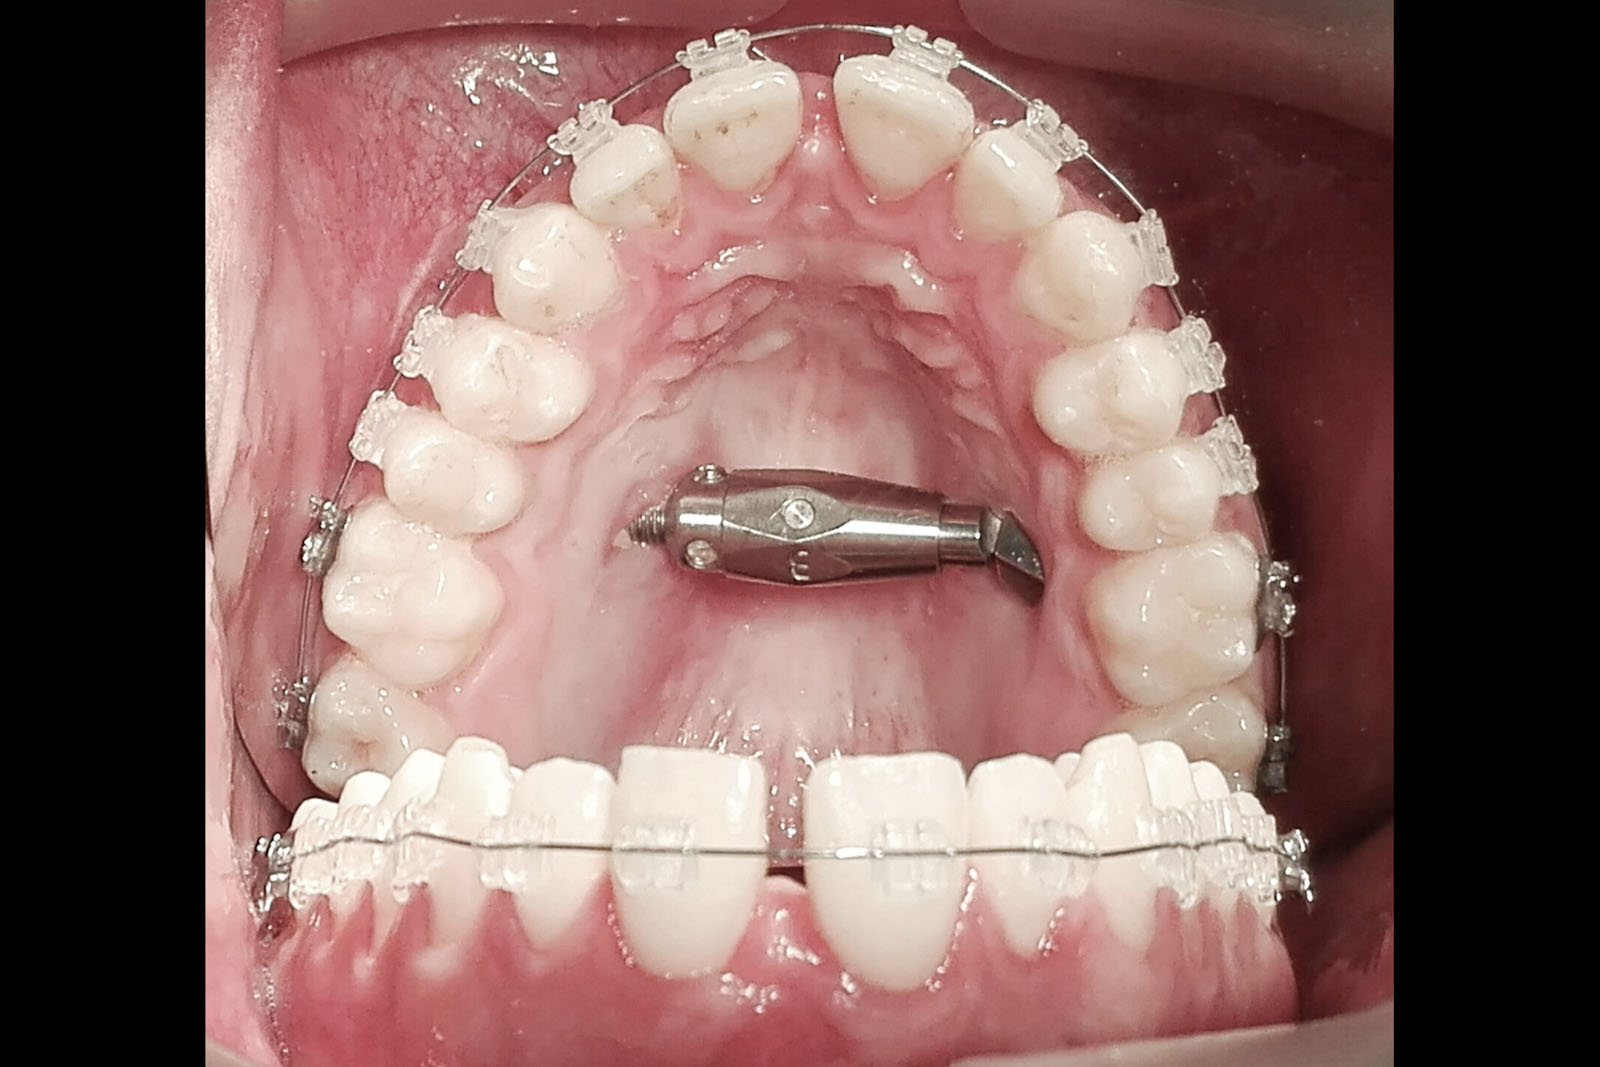

ZASTOSOWANIE DYSTRAKTORÓW KOSTNYCH ORAZ TECHNIK OSTEOGENEZY DYSTRAKCYJNEJ W ZAKRESIE WYROSTKA ZĘBODOŁOWEGO SZCZĘK I ŻUCHWY

Obecnie rzadko stosowana metoda odbudowy tkanki kostnej, która bazuje na naukowych podstawach z lat pięćdziesiątych ubiegłego stulecia. Prof. Ilizarov jako pierwszy opisał tę technikę, polegającą wówczas na wydłużaniu kości długich ludzkiego szkieletu. Metodę tę adaptowano dla potrzeb korekcji wad wrodzonych twarzowo-szczękowych oraz rekonstrukcji ubytków i deformacji kostnych w zakresie wyrostka zębodołowego szczęk i żuchwy.

Do wydłużenia i poprawy kształtu kości poddanej korekcie techniką osteogenezy dystrakcyjnej wykorzystuje się specjalne aparaty nazywane dystraktorami. Działają one poprzez rozkręcanie śrub, które aktywują proces wydłużania kości. W zależności od budowy dystraktora mogą one działać jedno-, dwu- lub trójwektorowo, czyli tylko wydłużać kość, rozciągać ją płaszczyznowo lub przestrzennie.

Aby zestaw rozciągający zadziałał, należy aktywować samą kość. Do aktywacji dochodzi na skutek nacięcia zewnętrznej, twardej blaszki kostnej, tzw. korowej, na zadanym kierunku lub pełnoprzekrojowego przecięcia kości. Po okresie kilku dni, gdy zaczyna się wytwarzać tkanka kostna bliznowata w miejscu przecięcia, rozpoczyna się aktywne rozkręcanie aparatu, a przez to wydłużanie wraz z wtórnym modelowaniem tkanki bliznowatej, która następnie mineralizuje się w strukturę kostną.